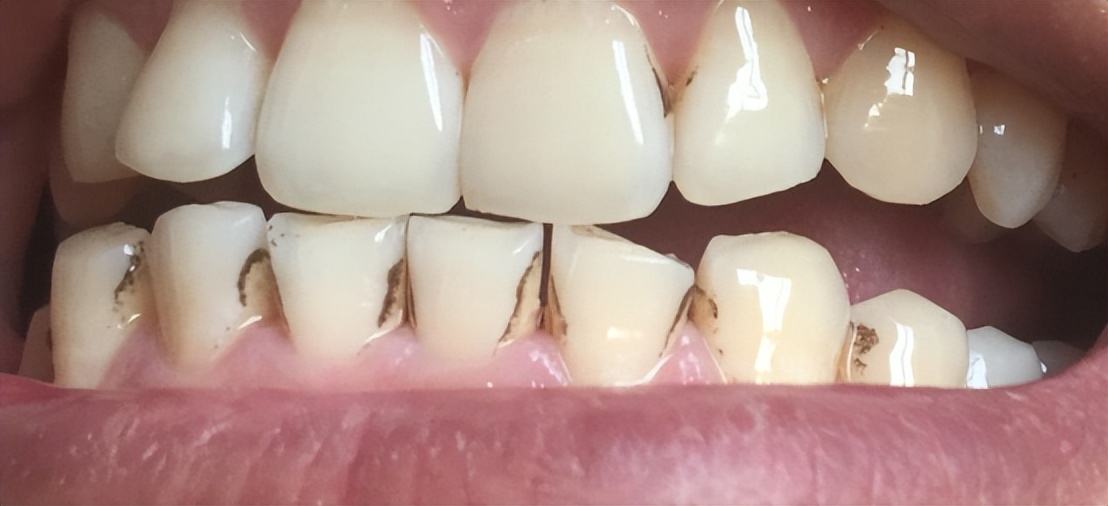

我国口腔问题普遍,九成以上的人有存在口腔问题(如下图),手动牙刷难以满足种植牙人群的口腔清洁需求,国人需要更强烈的洁牙工具,专业牙医建议种植牙人群使用电动牙刷、冲牙器。